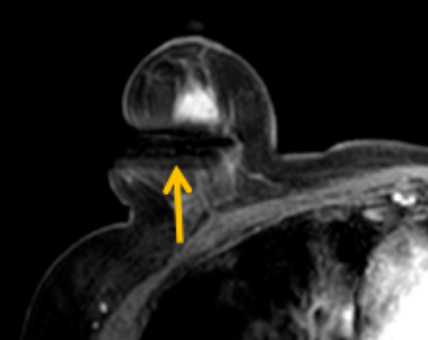

陳寶瑩評(píng)估圖像后發(fā)現(xiàn)病變?yōu)閮H僅在磁共振增強(qiáng)時(shí)顯示,為非腫塊樣病變,比較散,必須取得足夠多的組織才能確保病理檢查的準(zhǔn)確性,常用的核芯針活檢獲取的組織較少,因此最終確定了磁共振引導(dǎo)下行真空輔助抽吸旋切活檢。取得患者及家屬認(rèn)可后,陳寶瑩帶領(lǐng)團(tuán)隊(duì)開始進(jìn)行術(shù)前準(zhǔn)備。

針對(duì)患者乳房小固定難度大這一問(wèn)題,陳寶瑩通過(guò)巧妙體位和固定器的調(diào)整,順利固定好乳房。經(jīng)過(guò)磁共振多模態(tài)掃描,陳寶瑩找出病變活性成分相對(duì)集中區(qū)域,精準(zhǔn)確定穿刺路徑,置入引導(dǎo)針、旋切針,到位后多角度旋切取出足量組織,拔除旋切針后即時(shí)行磁共振掃描,精準(zhǔn)取得組織且術(shù)區(qū)出血很少,遂加壓包扎,整個(gè)過(guò)程非常順利,旋切活檢后患者回家休息。兩天后隨訪,李女士沒(méi)有任何不適,五天后皮膚上幾毫米的小切口已經(jīng)愈合。最終病理結(jié)果證實(shí)為乳腺導(dǎo)管原位癌,為早期乳腺癌,為患者后續(xù)針對(duì)性治療奠定了基礎(chǔ)。